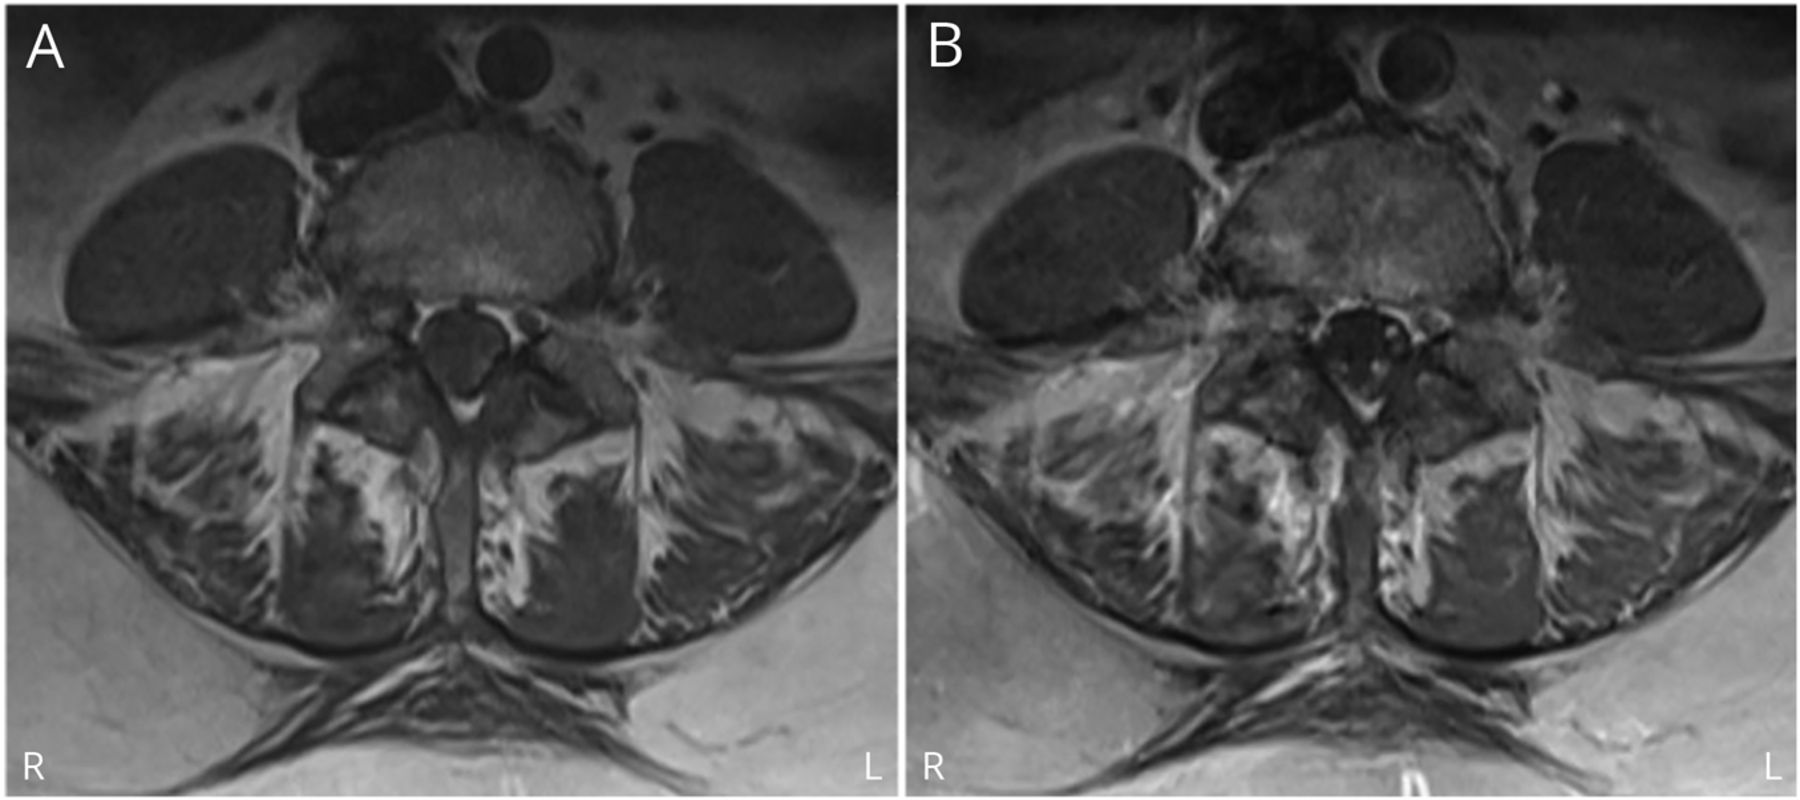

一个60岁的女人有偏头痛病史的她平时的健康状况,当她参加疫苗试验。逆转录酶聚合酶链反应(rt - pcr)测定SARS-CoV-2和抗体检测呈阴性筛选之前接种疫苗。她收到了疫苗在2020年12月10日。她仍远没有任何呼吸道和胃肠道症状,直到10天接种疫苗后,当她开始在她的后背和腿疼痛。有人看见她出现症状后进行的一项研究的访问4天(2020年12月24日)和当时的PCR分析SARS-CoV-2是负面的。第二天,她醒来,头痛,恶心,呕吐,和复视,她去了医院。神经系统检查正常,但她一夜之间治疗偏头痛。头痛和复视坚持出院后,12月27日,2020年,她被送到医院,这次是在神经学服务。首页考试那天显示左眼内斜眼中线的目光和双边眼部绑架赤字但强度、四肢感觉和反应都是正常的。到了第二天,她的症状已经发展到双边面部无力和麻木,反射消失,2/5疲软的双腿。 MRI of the lumbar spine demonstrated enhancement of the cauda equina (图)。脑部核磁共振是正常的。腰椎穿刺显示增加开启压力(29厘米H2O)和脑脊液蛋白升高(140 mg / dL), 9有核细胞,正常葡萄糖(63 mg / dL)。电生理学的研究2天入院后显示正常的复合肌肉和感觉神经动作电位和没有延迟响应(腓骨和胫骨F-waves后H-reflexes)的腿。针肌电图显示神经源性招聘在腿部肌肉(快速发射单元)。这些发现在GBS的最早的电生理学的异常。Antiganglioside抗体呈阴性。SARS-CoV-2 rt - pcr是在入学和重复了两次,导致负面的。她用静脉注射免疫球蛋白治疗2 g / kg / 2天开始于12月29日,2020年。她的力量慢慢改善,她出院康复入学后10天。